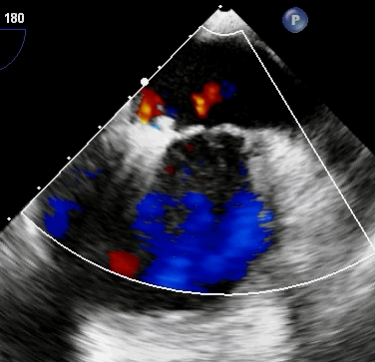

术后微量反流

术前,科室组织多学科会诊,由心脏大血管外科、心内科、麻醉科等多位专家共同讨论并一致认为,老人二尖瓣病变严重,同时合并有冠心病、心律失常、心功能不全等多种高危因素,已不适用外科手术,在微创下不开胸实施二尖瓣钳夹术是最佳选择。经手术团队充分缜密的术前准备,在超声引导下器械经股静脉穿刺房间隔,将MitraClip系统送入患者左心房,到达二尖瓣反流处,在经食道超声及DSA引导下,术者通过评估二尖瓣反流位置、抓捕位置、反流程度,精准夹合,成功植入2个二尖瓣夹。二尖瓣从术前的大量反流减轻到微量反流,肺静脉的逆流完全消失,血压从偏低恢复到正常状态,第二天即下床,术后第5天顺利出院。